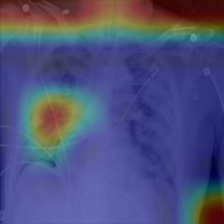

COVID data set. The potential of artificial intelligence and especially deep learning in medicine is huge (EJ., 2019). On the other hand, the medical domain is known to be badly affected by the presence of confounders (Jager et al., 2008; Smith & Nichols, 2018). In order to evaluate the potential of ProtoPDebug to help addressing this issue, we tested it on a challenging real-world problem from the medical imaging domain. The task is to recognize COVID-19 from chest radiographies. As shown in DeGrave et al. (2021), a classifier trained on this dataset heavily relies on confounders that correlate with the presence or absence of COVID. These confounders come from the image acquisition procedure or annotations on the image. We trained and tested ProtoPDebug on the same datasets used in DeGrave et al. (2021) using the data pipeline source code (cod, 2021a). To simplify the identification of confounders, we focused on a binary classification task, discriminating COVID-positive images from images without any pathology. Given the extremely high inter-annotator agreement of the CUB5nat experiment, this experiment was conducted internally in our lab. We leave a crowdsourced evaluation to an extended version of this work.

Results. Fig. 5 reports the (non-zero activation) prototypes of ProtoPDebug at different correction rounds. As for Fig. 4 (left), the left-most column corresponds to the prototypes learned by ProtoPNets. Note that for each prototype, the supervision is given to the 10 most-activated images (). Penalized confounders have been extracted from images on which the prototype has non-zero activation, because they influence the classification. However, the patches of the images to remember are extracted even if the activation is zero, in order to force the prototype to increase the activation on them thanks to the remembering loss. Eventually, ProtoPDebug manages to learn non-confounded prototypes, resulting in substantially improved test classification performance. The test goes from 0.26 of ProtoPNets (first column) to 0.54 at the end of the debugging process.